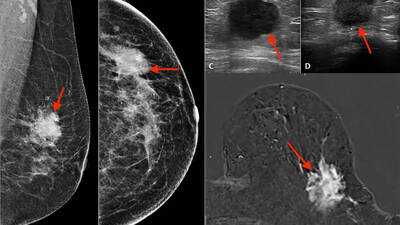

ILC originates in the lobules (milk-producing glands) and often behaves differently than the more common invasive ductal carcinoma (IDC). Its growth is typically more diffuse and less likely to form a firm, well-defined tumor, which can delay detection. Strikingly, although ILC accounts for just over 10% of breast cancer cases, its long-term outcomes may lag behind IDC in metastatic or advanced disease. Experts warn that ILC’s subtle presentation contributes to underdiagnosis and slower therapy responses. Because of its stealthy behavior, many ILCs are diagnosed later or discovered only via imaging or biopsy, rather than being felt as a lump.

Screening and detection patterns: Traditional mammograms sometimes miss ILC’s diffuse growth, leading to later diagnoses. As imaging improves (e.g., MRI, tomosynthesis), more cases may be found.